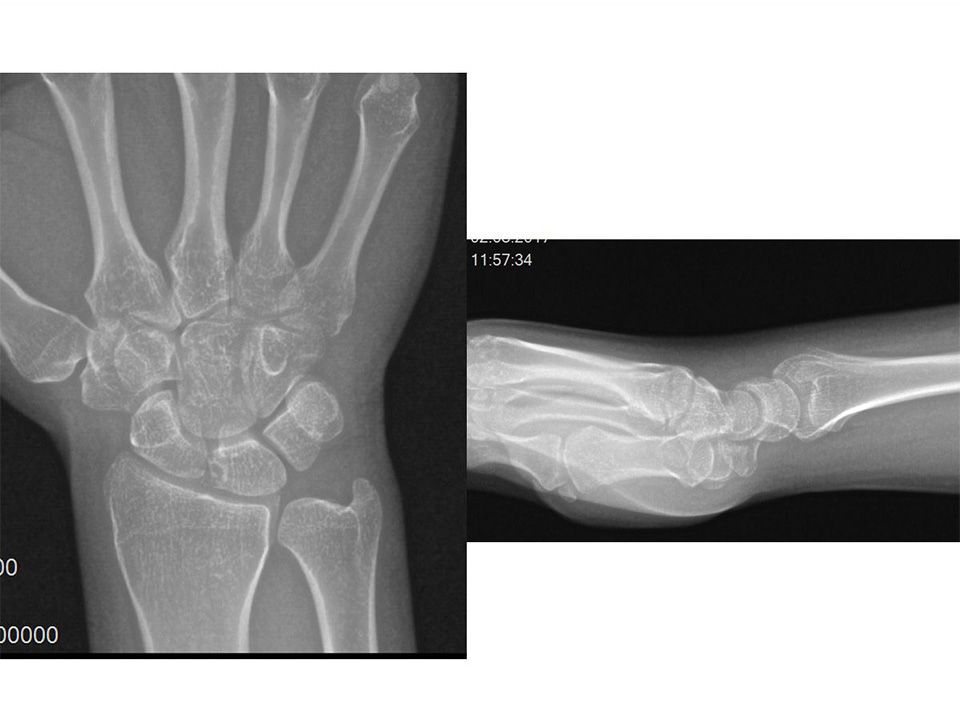

37 yaş, erkek, mobilyacı, sağ el dominant2-3 yıldır mevcut olan sol el bileği ağrısıLunat dorsalinde hassasiyetEl bilek fleksiyonu 50*, ekstansiyonu 50* ve ağrısız